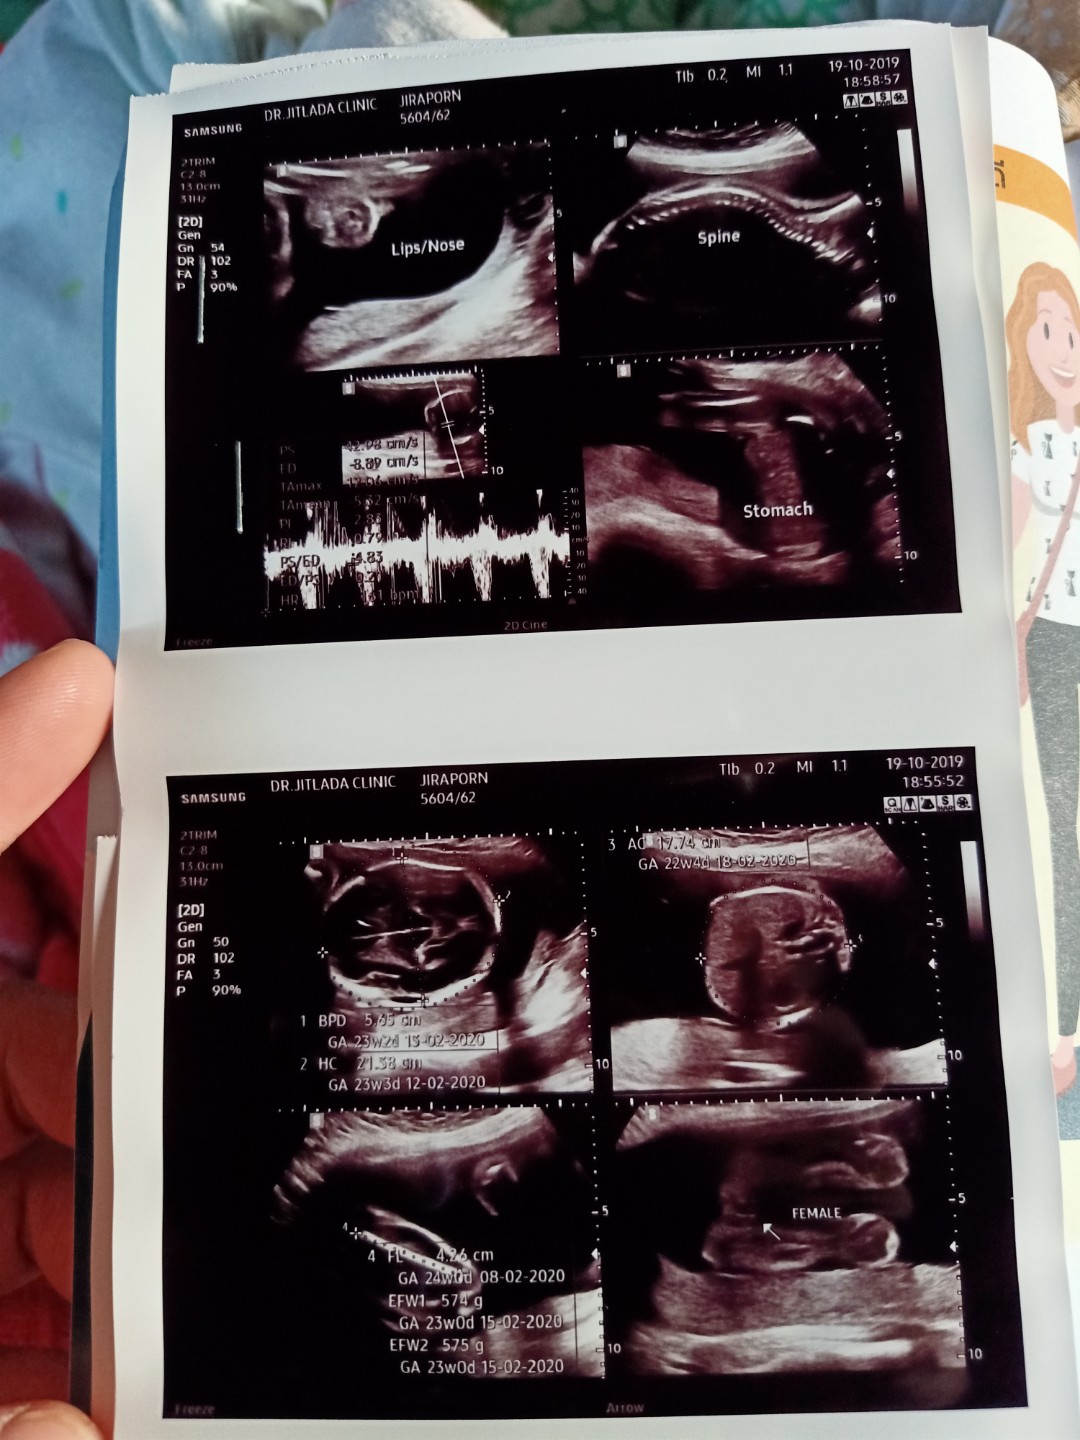

อ้าขาเลย ผู้หญิงค่ะ

มีกลีบเหมือนกันจ้า

บ้านนี้กลีบค่ะ